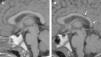

La histiocitosis de células de Langerhans (HCL) es una enfermedad rara caracterizada por la acumulación en los tejidos de células dendríticas anómalas similares a las células de Langerhans. La presentación clínica varía desde la aparición de una lesión ósea única hasta la afectación multisistémica. La implicación del sistema nervioso central (SNC), manifestada como diabetes insípida secundaria a afectación hipofisaria, es conocida desde la descripción original de la enfermedad. En la actualidad, se diferencian 2 tipos de lesiones del SNC: las lesiones seudotumorales, con infiltración por las células de Langerhans, cuya manifestación más frecuente es la infiltración hipofisaria, y otras, de más reciente descripción, las lesiones neurodegenerativas del SNC, asociadas a deterioro neurológico, que constituyen una complicación de la enfermedad de causa discutida. Nuestro objetivo es describir las manifestaciones radiológicas de la HCL en el SNC en los pacientes pediátricos.

Langerhans cell histiocytosis (LCH) is a rare disease characterized by the accumulation within tissues of anomalous dendritic cells similar to Langerhans cells. The clinical presentation varies, ranging from the appearance of a single bone lesion to multisystemic involvement. Central nervous system (CNS) involvement, manifesting as diabetes insipidus secondary to pituitary involvement, has been known since the original description of the disease. Two types of CNS lesions are currently differentiated. The first, pseudotumoral lesions with infiltration by Langerhans cells, most commonly manifests as pituitary infiltration. The second, described more recently, consists of neurodegenerative lesions of the CNS associated with neurologic deterioration. This second type of lesion constitutes a complication of the disease; however, there is no consensus about the cause of this complication. Our objective was to describe the radiologic manifestations of LCH in the CNS in pediatric patients.